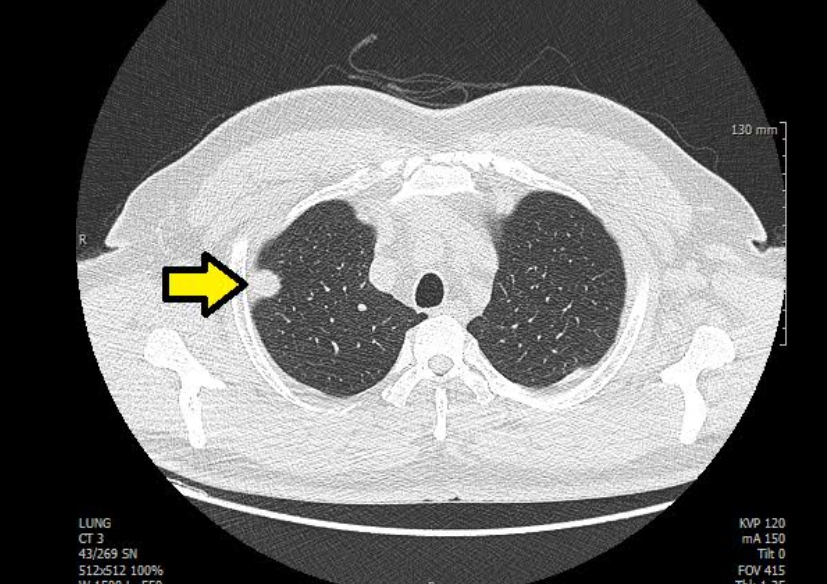

폐렴은 엑스레이에서 가장 자주 발견되는 질환 중 하나예요. 정상적인 폐는 까맣게 보이지만, 염증이 생기면 하얗게 변합니다. 의사들은 이를 보고 ‘침윤(염증이 번진 상태)’이라고 표현해요.

흉부 엑스레이로 알수있는것 폐렴의 종류에 따라 모양도 달라요. 한쪽 폐 전체가 하얗게 보이면 ‘엽성 폐렴’, 군데군데 얼룩처럼 보이면 ‘기관지 폐렴’일 수 있어요. 예전에 제 친구가 독감 후 기침이 너무 오래가서 병원에 갔는데, 엑스레이에 하얀 구름처럼 음영이 보여 폐렴 진단을 받았죠. 약을 꾸준히 먹고 다시 찍었을 땐 그 구름이 걷힌 것처럼 깨끗했어요. 이렇게 눈에 보이는 회복의 흔적이 참 다행스럽습니다.